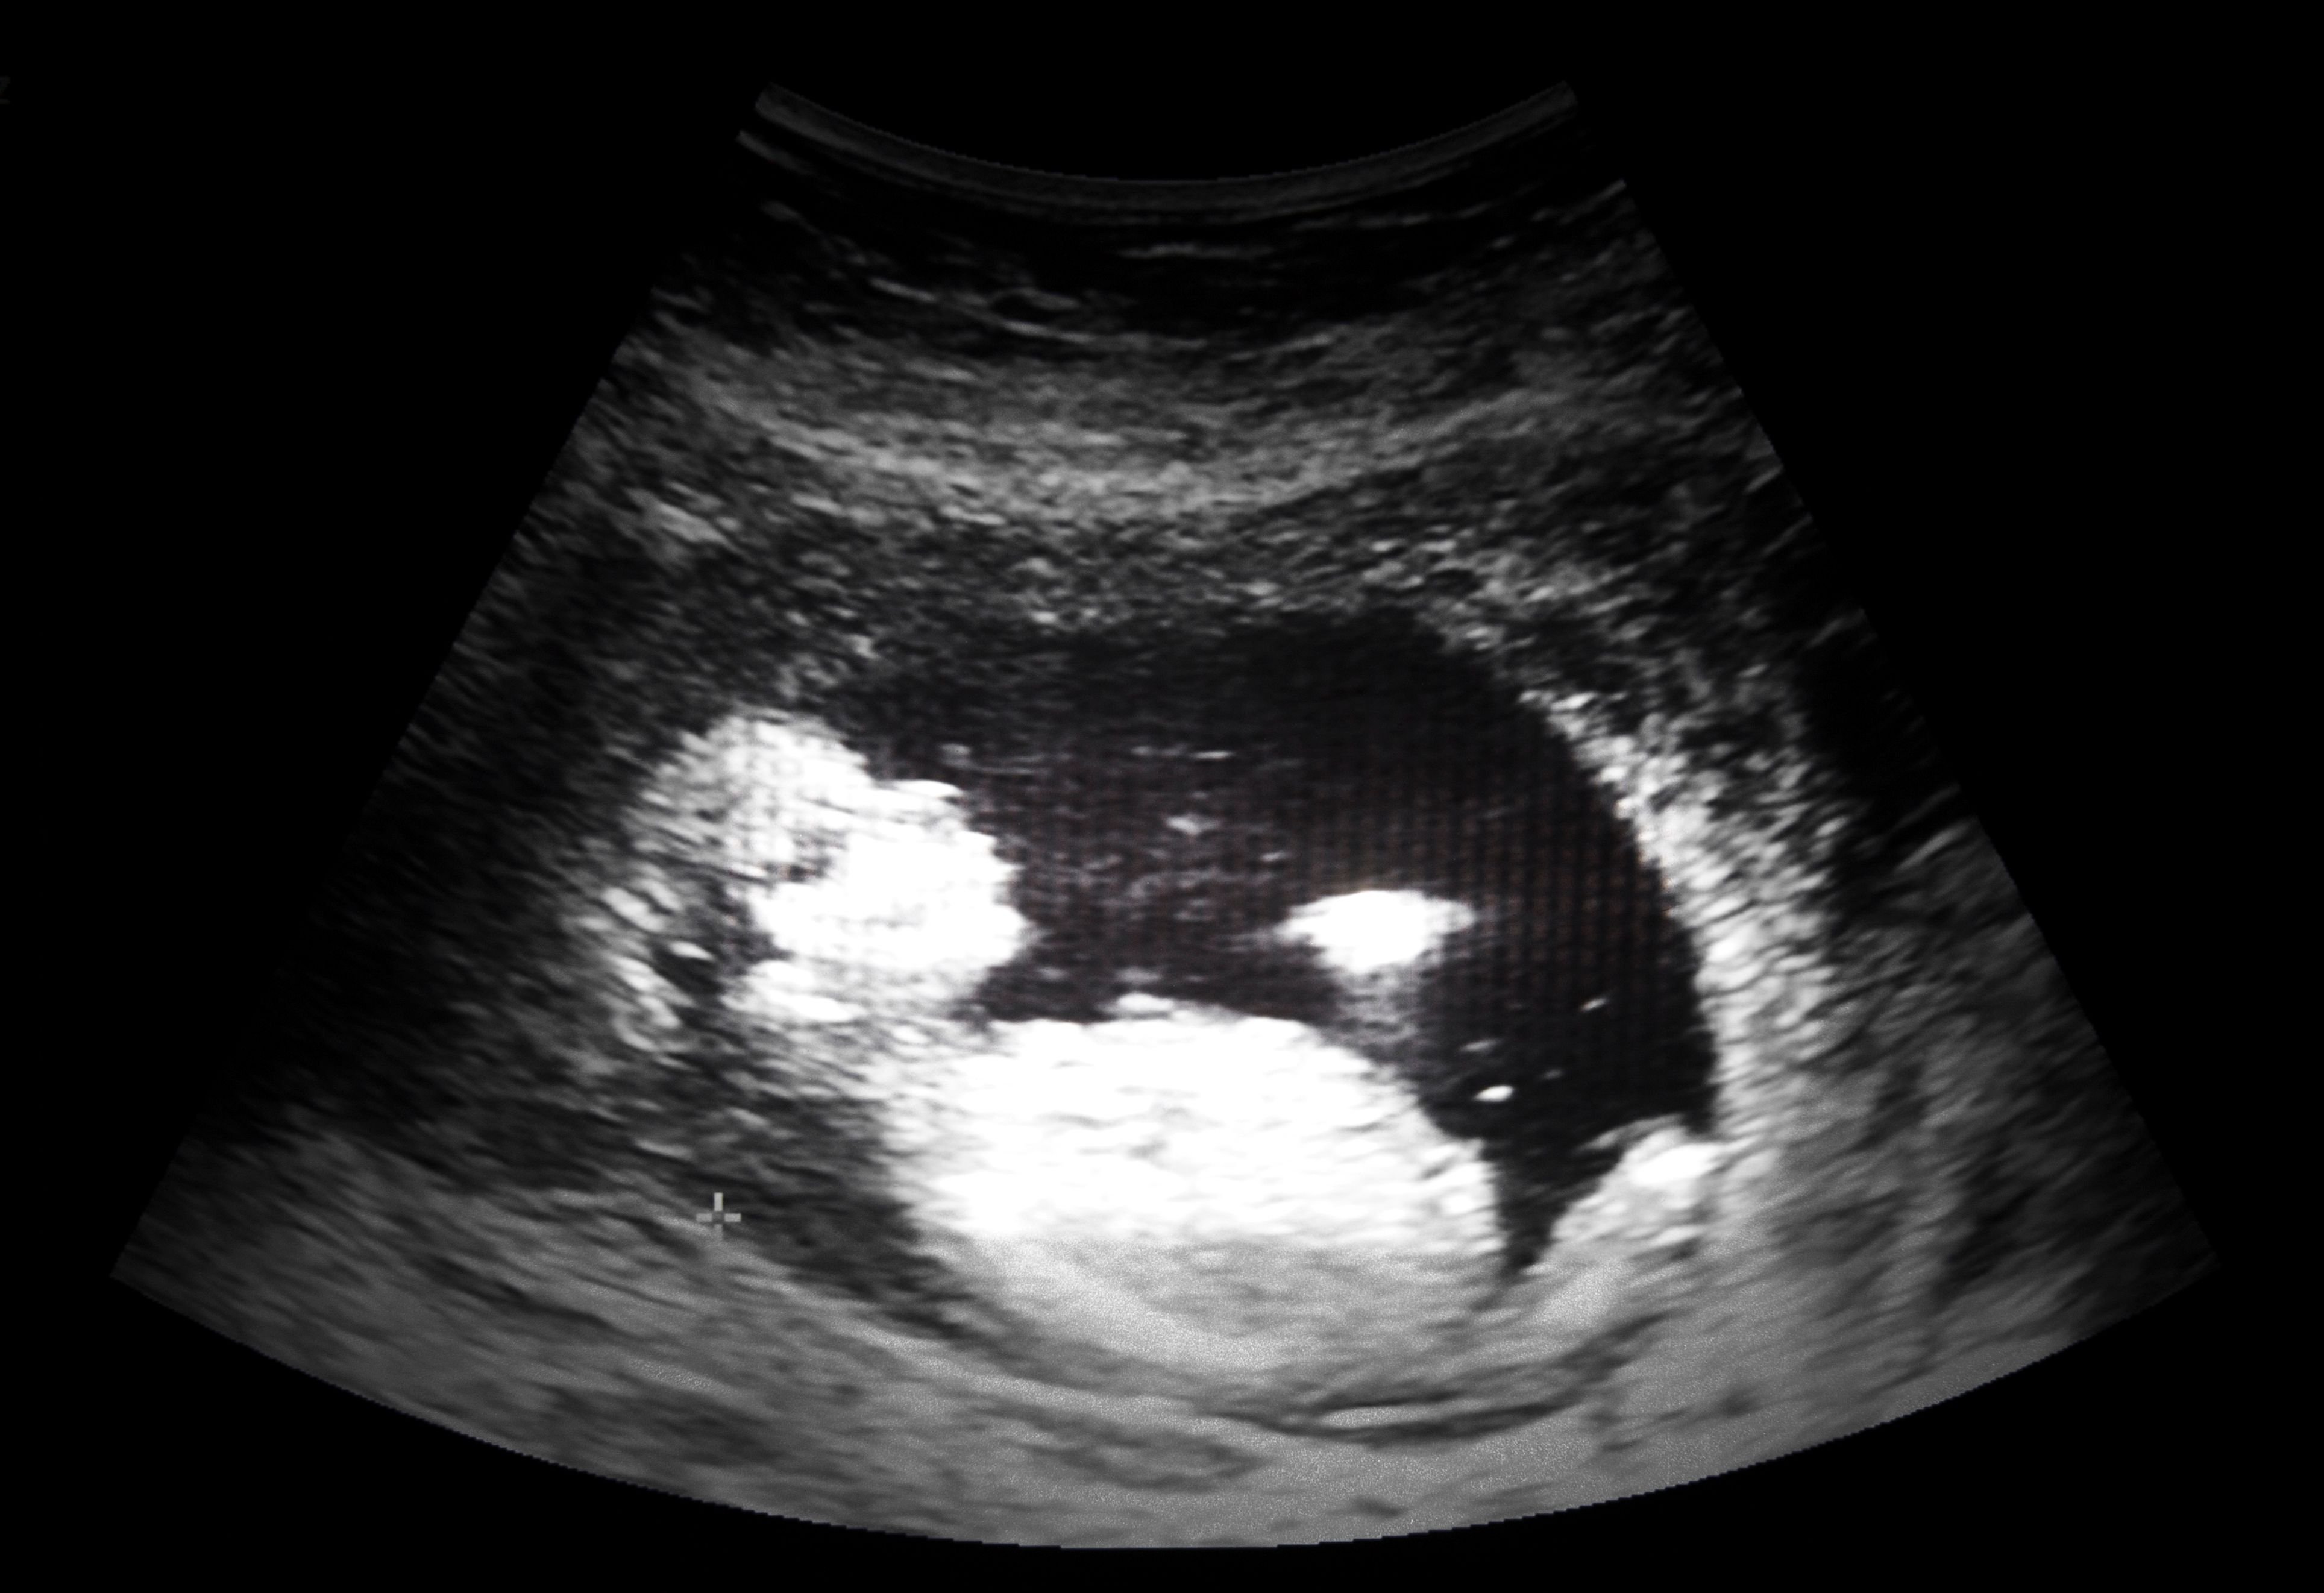

In der 36. Woche verlor Amna Bibi ihre ungeborene Tochter. (Symbolbild)

ultrasound film of thirteen week fetus